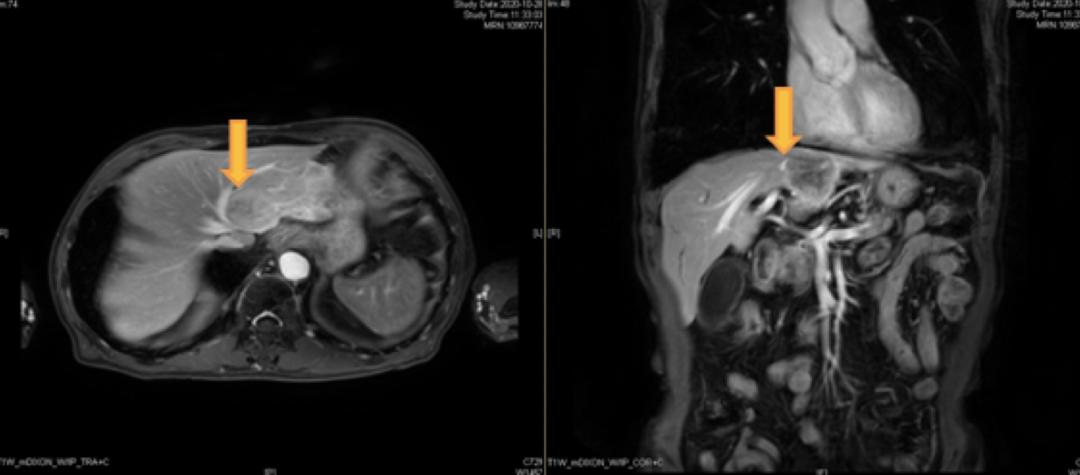

2020-10-28上腹部MRI:肝S2段转移瘤

肝S2段内见一长T2 长T1信号,边界清,约42mm*31mm,增强后呈环形强化,弥散受限。考虑转移瘤。

首诊10.28(左):42mm*31mm;四治疗后3.10(右):20.8mm*12.9mm明显缩小